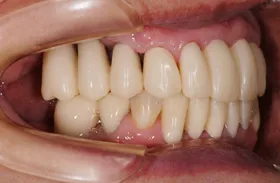

他院で「歯槽膿漏は治らない」と言われ、当院にご来院されました。歯が乱ぐいのため、歯並びもよくしたい、下は歯を既に失っているので噛めるようにもなりたい、またコーラスをされていて人前で口をあけることが多いので、できるだけ見た目を意識した治療をしてほしいとのご要望でした。

■治療(仮歯装着)後